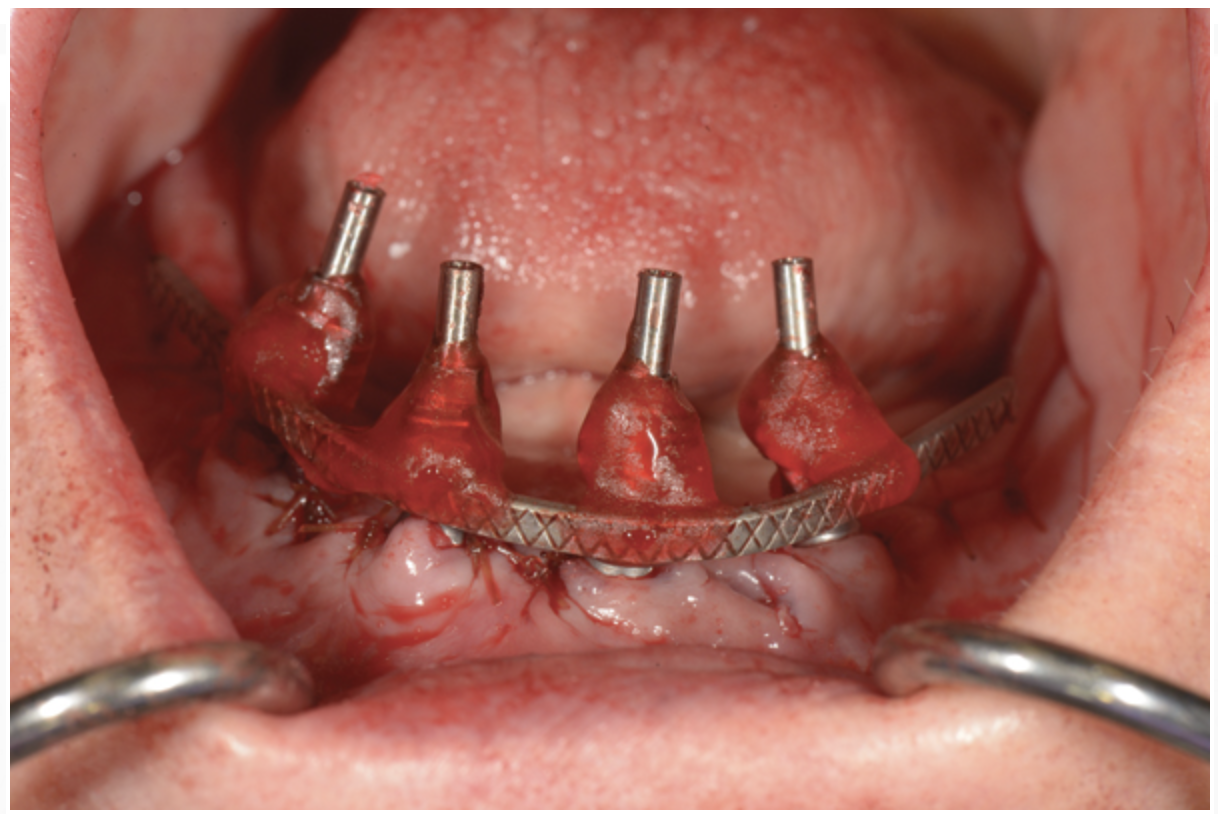

To start, a surgical impression is performed. Open-tray impression copings are secured to the restorative abutments, and a denture-strengthening bar is attached to the copings using a low-expansion pattern resin. The “salt and pepper” technique is used for precise control of the material, thereby avoiding contact with the surgery site and more effectively controlling working time. A plastic impression tray is modified in the occlusal areas where the impression copings will emerge and is tried-in to verify that there are no interferences. Polyvinylsiloxane impression putty is mixed and adapted over the impression copings and denture-strengthening bar. Impression material is also placed in the tray prior to seating. The impression coping screws are exposed and disengaged, allowing the impression to be easily removed. Rigid stabilization of the copings in the impression is verified (Figure 10 through Figure 12). The surgical index is performed using the same provisional prosthesis guide used during the surgery. Only the two anterior implants are indexed. The provisional prosthesis guide is seated to verify the absence of interferences with the two anterior temporary cylinders, and cold-cure acrylic material is applied through the access windows using a “salt and pepper” technique (Figure 13). The prosthesis is held in place with light pressure on the prosthesis guide over the palate or the posterior lingual mandibular ridge until the resin is cured. The VDO is verified after guiding the patient into occlusion with a bite registration recorded in the lab. Esthetic and functional parameters are verified, and the indexed prosthesis is removed with the attached temporary cylinders, and it is then disinfected in cold sterile solution.

Fig 10. Surgical impression—Open-tray impression copings are secured and splinted with a denture-strengthening bar using low-expansion pattern resin.

Figure 10

Fig 11. Surgical impression—Modified plastic impression tray seated to verify that there are no interferences with the copings or the bar.

Figure 11

Fig 12. Surgical impression—After impression putty is adapted around the impression copings and bar, the tray is filled with impression material and seated, the copings are exposed, and the retention screws are disengaged to allow the impression to be easily pulled.

Figure 12